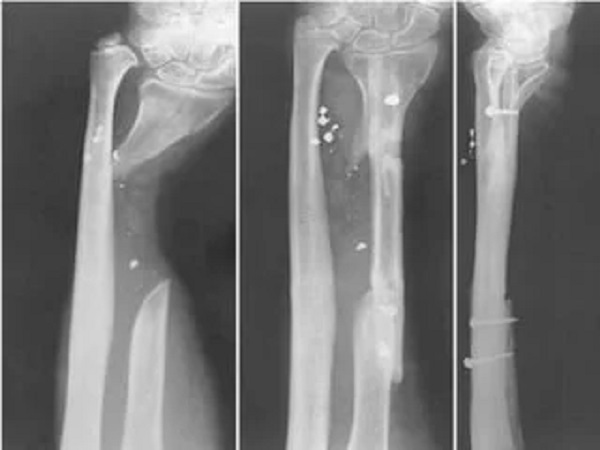

Kemik erimesinin kişinin yaşam kalitesini bozan, insan sağlığını tehdit eden bir durum olduğunu dile getiren Doç. Dr. Mehtap Bozkurt, hastalığın belirtilerini şöyle anlattı: "Kemik erimesi sinsi bir hastalıktır ve erken dönemde hiçbir klinik bulgu vermez. Genellikle kazalara bağlı küçük travmalar sonrası kırıkların oluşması ile kendini gösterir. Kırıklar çoğunlukla omurga, kaburga, kalça ve el bileğinde gelişir. Omurga kemiklerindeki küçük kırıklardan kaynaklanan çökmelere bağlı olarak boyda kısalma ve sırtta kamburluğun artması gibi gözle görülebilir değişiklikler gelişebilir"

Ani başlayan şiddetli sırt ağrısının ve özellikle gece ağrısının osteoporoz bağlı kemik kırıkları açısından uyarıcı bir işaret olduğunu ifade eden Doç. Dr. Mehtap Bozkurt, "Bunlar içinde komplikasyon riskinin yüksek olması nedeniyle kalça kırıkları önemli bir yer kaplamaktadır. Özellikle yaşlı hastalarda kemik kaynama problemlerinin fazla olması nedeniyle yatağa bağımlı kalma riski yüksektir. Bir kere kırıklar başladı mı yeni kırıkların da oluşması kaçınılmazdır. Bu aşamaya gelmeden önce menopoza giren hastalarda kemik erimesini önleyici yaklaşım ve gerekirse kemik yoğunluğunu artıracak tedavilerle kırıkların önüne geçilmesi önemlidir. Yapılan çalışmalar kalsiyum ve D vitamini takviyesinin osteoporoza bağlı oluşan kırıkların tedavisinde ve önlenmesinde oldukça etkili olduğunu göstermiştir" dedi.